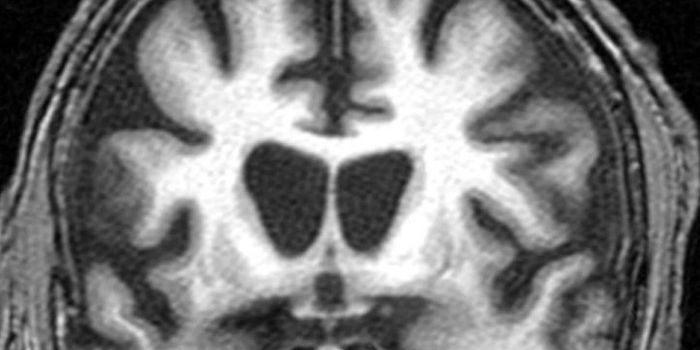

SEP 19, 2019NeuroscienceResearchers from the University of California have found a low-cost, non-invasive method to aid in diagnosing Alzheimer& ...

SEP 07, 2019NeuroscienceMRI scans give us pictures of the brain that depict the physical structure of brain tissue. Now, researchers discovered ...

AUG 02, 2022NeuroscienceRecent allegations of research misconduct have called years of Alzheimer's research into question. The controversy surro ...